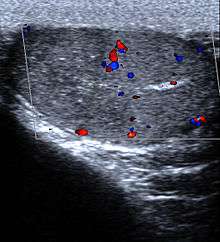

- Spleen: Splenic infarction occurs when the splenic artery or one of its branches are occluded, for example by a blood clot. Although it can occur asymptomatically, the typical symptom is severe pain in the left upper quadrant of the abdomen, sometimes radiating to the left shoulder. Fever and chills develop in some cases.[8] It has to be differentiated from other causes of acute abdomen.